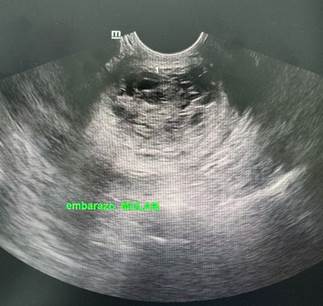

Figura 1. Ecografía transvaginal se reporta embarazo molar.

Reporte: Se realiza ecografía transvaginal donde se evidencia: útero en retroversión que mide 14 cm x 12cm, se evidencia imágenes quísticas correspondiente a placenta en interior de útero que ocupa casi en su totalidad, no se evidencia producto, no se evidencia líquido amniótico.

IDG: Mola hidatiforme.